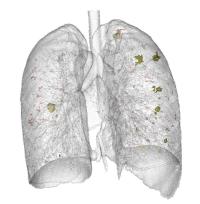

Lung Nodule Detection

Nodule missed by radiologist but detected by a computer

A nodule missed by radiologist but detected by computer

Lu L, Tan Y, Schwartz LH and Zhao B. Hybrid detection of lung nodules on CT scan images. Med Phys. 2015;42:5042-54. (Study interviewed and reported by AuntMinnie.com in October 2015)

Zhao B, Gamsu G, Ginsberg MS, Jiang L, Schwartz LH. Automated detection of small lung nodules on CT utilizing a local density maximum algorithm. J. Applied Clinical Medical Physics 2003; 4(3):248-260.